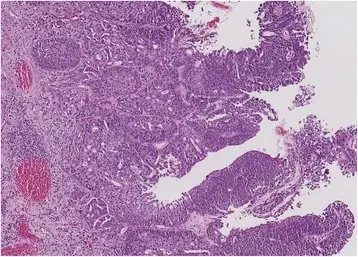

Urothelial Carcinoma

Urothelial carcinoma is also known as transitional cell carcinoma.

The epithelial lining of the renal pelvis, ureter, bladder, or urethra is the source of this malignant tumor.

Urothelial carcinoma is the most typical type of bladder cancer.

Urothelial carcinoma arises via two distinct pathways:

- Flat

- Papillary

Papillary urothelial carcinoma initially appears as a low-grade papillary tumor, advances to a high-grade papillary tumor, then invades, and is not linked to early p53 mutations.

A field defect is when a tumor recurs and is frequently multifocal in nature.